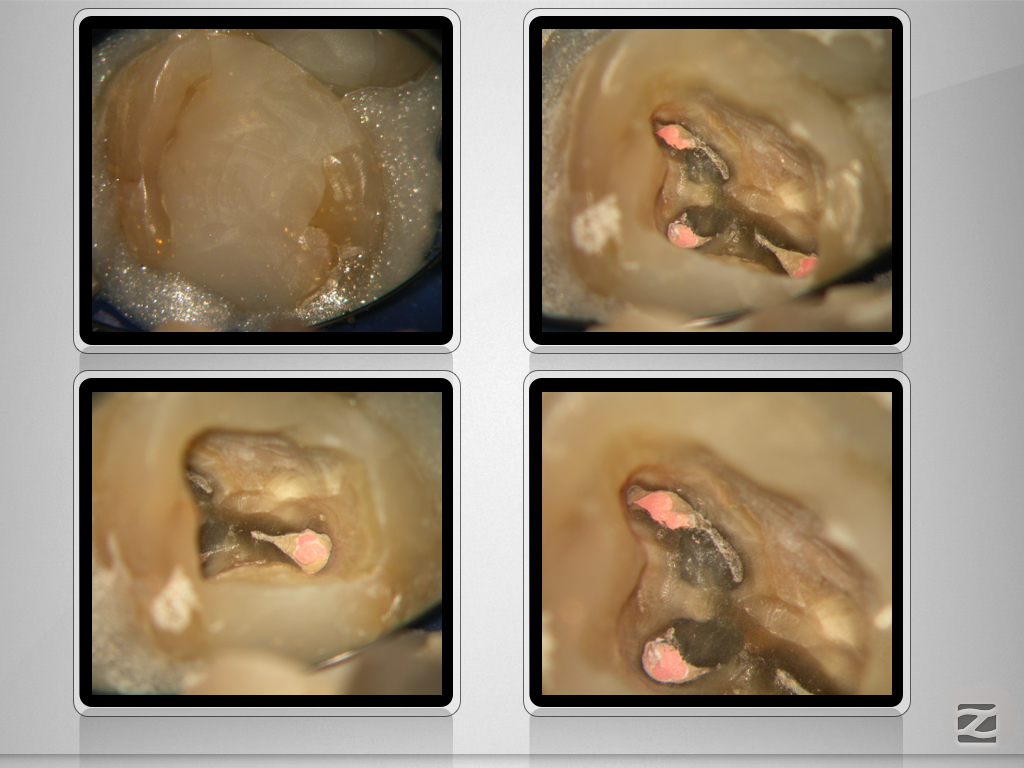

27D.005

Die gute alte Hedströmfeile